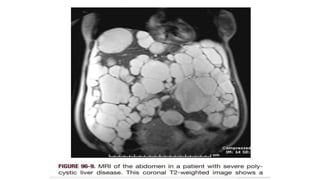

Polycystic Liver Disease

• PCLD is a rare condition in which multiple

cysts form in the hepatic parenchyma

• PCLD usually presents in association with

ADPKD

• Cysts range in diameter from a few millimeters

to 10 cm or more.

• They contain clear, colorless, or straw-colored fluid

• The cysts usually are asymptomatic and

discovered incidentally during upper abdominal

imaging.

• Symptoms occur in patients with more

numerous

and larger cysts (10% to 15% of patients,

usually women), generally with markedly enlarged

livers.

• Protuberant abdomen

• Inability to bend over, and shortness of breath

• Severe pain: rupture or infection of a cyst, bleeding

into a cyst, or torsion of a pedunculated cyst

• Jaundice is evident in approximately 5% of

patients

• Ascites: is the result of portal hypertension